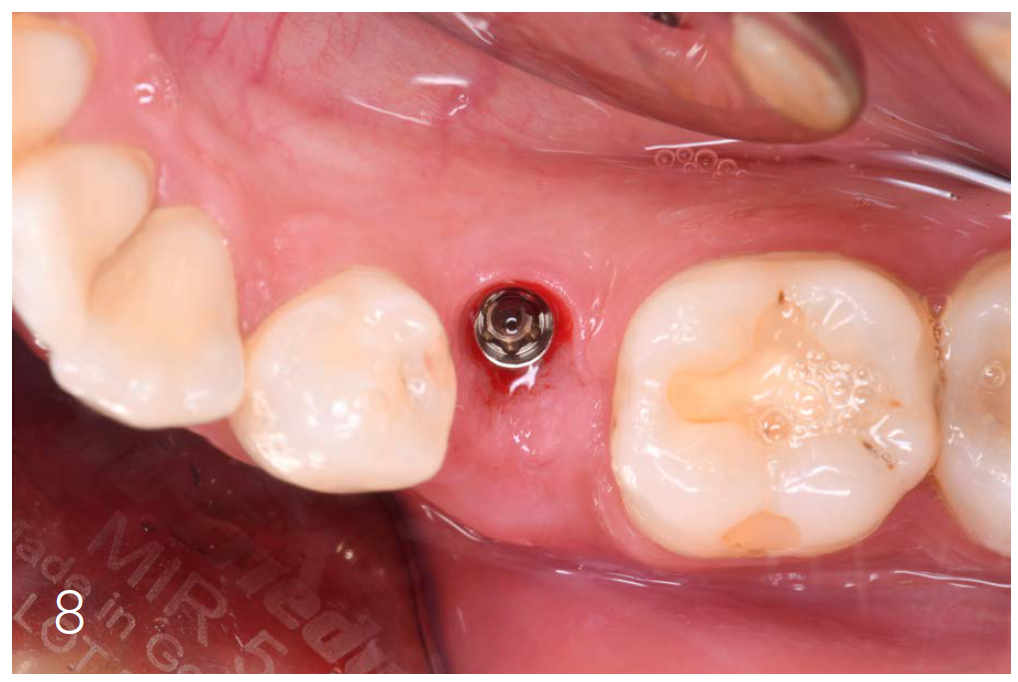

Figures 7 and 8: Clinical situation after 6 months

|